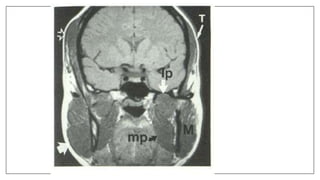

Normal anatomy

Pathologies